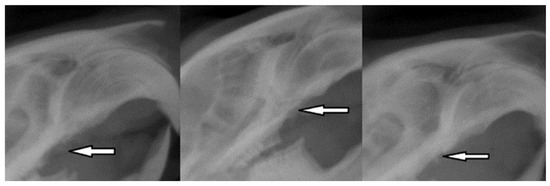

After the first exposure, the radiological results showed optimal bone regeneration, the uniform implant bed, and bone density within physiological limits (Figure 13).

Figure 13. Radiographic images 30 days after tooth extraction showing alveolar bone regeneration (white arrow).

In peri-implant disease, radiographic images can assess the height of the alveolar bone in relation to the implant structure. In the case of our experiment, after the completion of the six weeks of bacterial contamination, it was possible to observe the displacement of the implants from the position parallel to the roots of the collateral teeth and a reduction in the bone density at the edge of the alveolar ridge (Figure 15).

Figure 15. Radiological appearance of the implants at the end of the period of oral contamination.